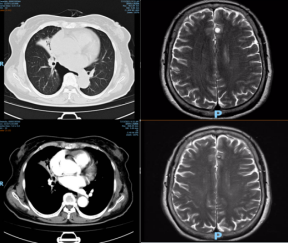

第一个病例为深圳市人民医院呼吸疾病研究所金常娥医师带来的广泛期小细胞肺癌一线治疗病例。患者主因“反复咳嗽半年,伴气喘、痰中带血3月”于2020年04月27日入院。入院后完善检查诊断为右肺小细胞癌伴脑转移(广泛期)。2021年6月3日始一线给予“阿替利珠单抗+依托泊苷+卡铂”方案治疗4周期,复查右肺及脑部病灶缩小,疗效PR。后续行阿替利珠单抗维持治疗14个月,肺部病灶继续缩小,脑部病灶消失。各位专家一致认为这是一例广泛期小细胞肺癌治疗的成功病例。根据Impower133研究,阿替利珠单抗+依托泊苷/卡铂对比传统化疗使疾病进展风险下降23% ,1年PFS率翻倍。而本病例中患者治疗至今17个月PFS时间仍未达到,无疑是免疫联合化疗治疗广泛期小细胞肺癌的经典案例。然而,专家也提醒到,此病例与其他广泛期小细胞肺癌病例不同,肺部病灶相对局限,仅有同侧肺门淋巴结转移,而脑部仅出现单发转移灶,且无其他脏器的转移,此时应该强调局部放疗的作用,尽早行胸部及脑部放疗。另外,也有专家提出,目前的临床研究是免疫治疗维持1年,延长免疫维持时间会增加患者的经济负担及毒副反应发生的风险,但是否会延长生存期尚不清楚,因此需要斟酌和探索。

第三个病例为襄阳市襄州区人民医院肿瘤科杨璞医师带来的左肺小细胞肺癌伴多发转移的病例。患者诊断为左肺小细胞广泛期cT4N3M1(双肺、多发肝、多发脑)。一线2020年3月30日-7月23日“依托泊苷+卡铂”方案化疗6周期,阿替利珠单抗治疗3周期,脑部病灶消失,肺部及肝脏病灶缩小。2020年8月脑部病灶进展,患者拒绝脑部放疗,而选择“阿替利珠单抗+依托泊苷+卡铂”方案治疗,此时脑部病灶再次消失,于2020年11月行脑部放疗,后续免疫维持治疗。2021年8月脑部病灶再次进展,肺部病灶及肝脏病灶稳定,先后尝试阿替利珠单抗联合“伊立替康+卡铂”化疗及安罗替尼治疗脑部病灶仍持续增大。目前正行“阿替利珠单抗+安罗替尼+替莫唑胺”治疗。杨璞医师汇报完病例后提出,目前患者主要是脑部病灶进展,能否行脑部二程放疗。针对这个问题,专家认为不推荐再次行脑部放疗,主要基于以下两点考虑:(1)二程放疗一般推荐在第一次放疗有效的前提下实施,但此患者第一次放疗是在脑部病灶消失的情况下完成的,无法评估脑部放疗的疗效,因而无法预估二程放疗的效果;同时,二程放疗的毒性会增加。在疗效未知、副反应增加的情况下,选择二程放疗的获益风险比较低。(2)患者两次药物治疗后脑部病灶疗效评估均达到CR,提示对药物治疗敏感,可以考虑继续药物治疗。最后,胡艳萍教授总结到近四十年来小细胞肺癌的治疗并无进展,直至免疫治疗的应用才带来突破。从目前临床研究数据看,仅PD-L1抑制剂可带来生存获益,而PD-1抑制剂效果不佳。同时,胡教授也提到,本次肺癌MDT交流会亮点是有两个来自呼吸科医师分享的病例,这有助于加强各专业的交叉融合,更有助于提高非肿瘤专科肺癌规范化诊疗水平。感谢各个医院提供的精彩的MDT病例,感谢各位专家的热烈讨论,希望今后多开展MDT团队交流,加强肺癌规范化联合诊疗,为患者带来更大获益。